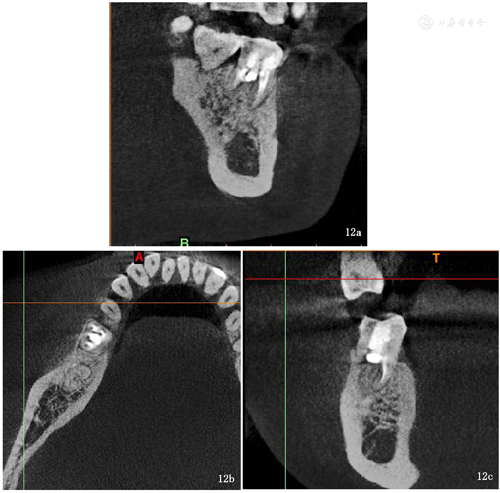

术后3个月复诊(2021年8月31日),患者自述高嵌体修复治疗后患牙未见明显异常,咬合正常,无松动。检查: 46高嵌体完好无破损,边缘密合,无松动,叩诊(-),咬诊(-),无咬合高点,牙龈颜色正常(图10),行局部小视野CT示:根尖周组织暗影明显缩小,远中根管穿孔区及近中根管壁穿孔区暗影较上次复诊X线片对比骨密度明显增高,暗影减轻,牙周膜间隙较上次恢复,余未见明显异常(图11、图12)。继续随访中。